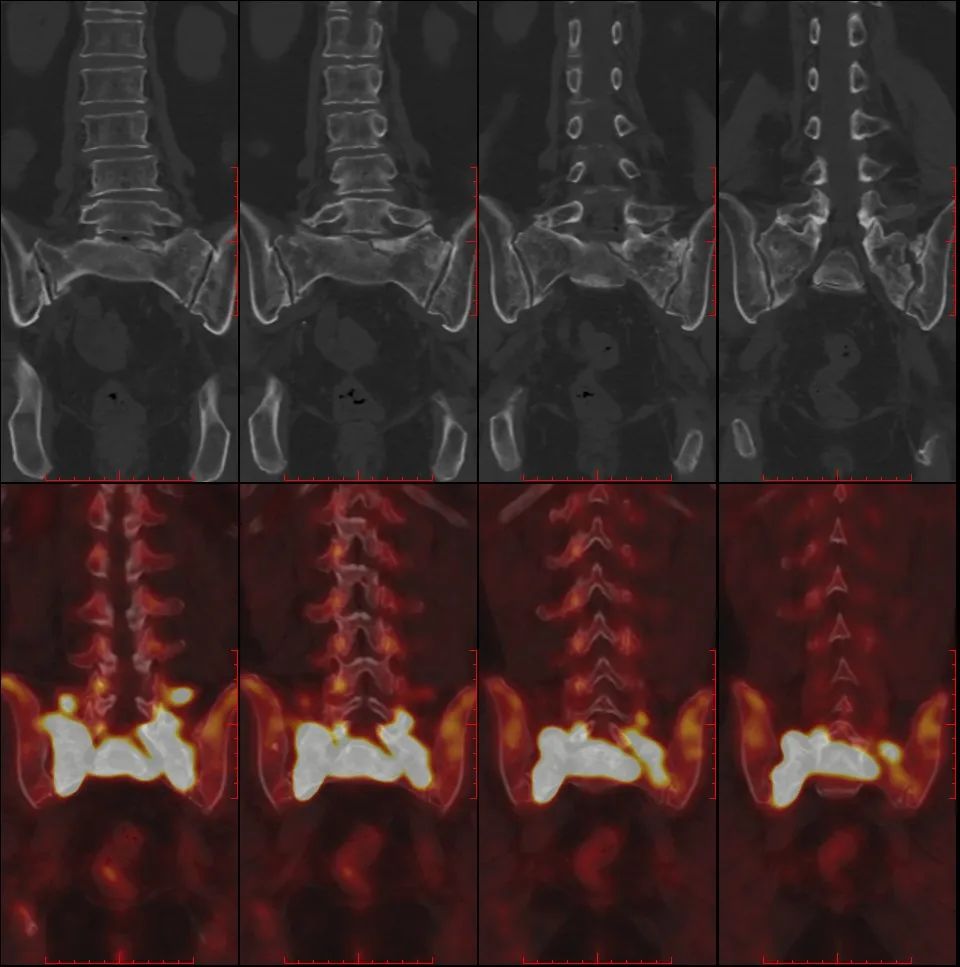

骶骨机能不全骨折 PET/CT 表现

骶骨机能不全骨折的典型 18F-FDG PET/CT 表现为平行于骶髂关节的骨折线伴 FDG 摄取轻中度增高,PET/CT 显示病变的 FDG 摄取特征及形态学改变与转移瘤的鉴别诊断有重要价值。

女,55 岁,宫颈癌放化疗后 5 年发生骶骨机能不全骨折。PET/CT 骶骨横断面(A)、冠状面(B)显示双侧骶骨翼平行于骶髂关节骨折线,放射性摄取弥漫性轻度增高,沿骨折线处为著(箭);矢状面(C)显示骶骨体横行硬化骨折线,轻度 FDG 摄取(箭)